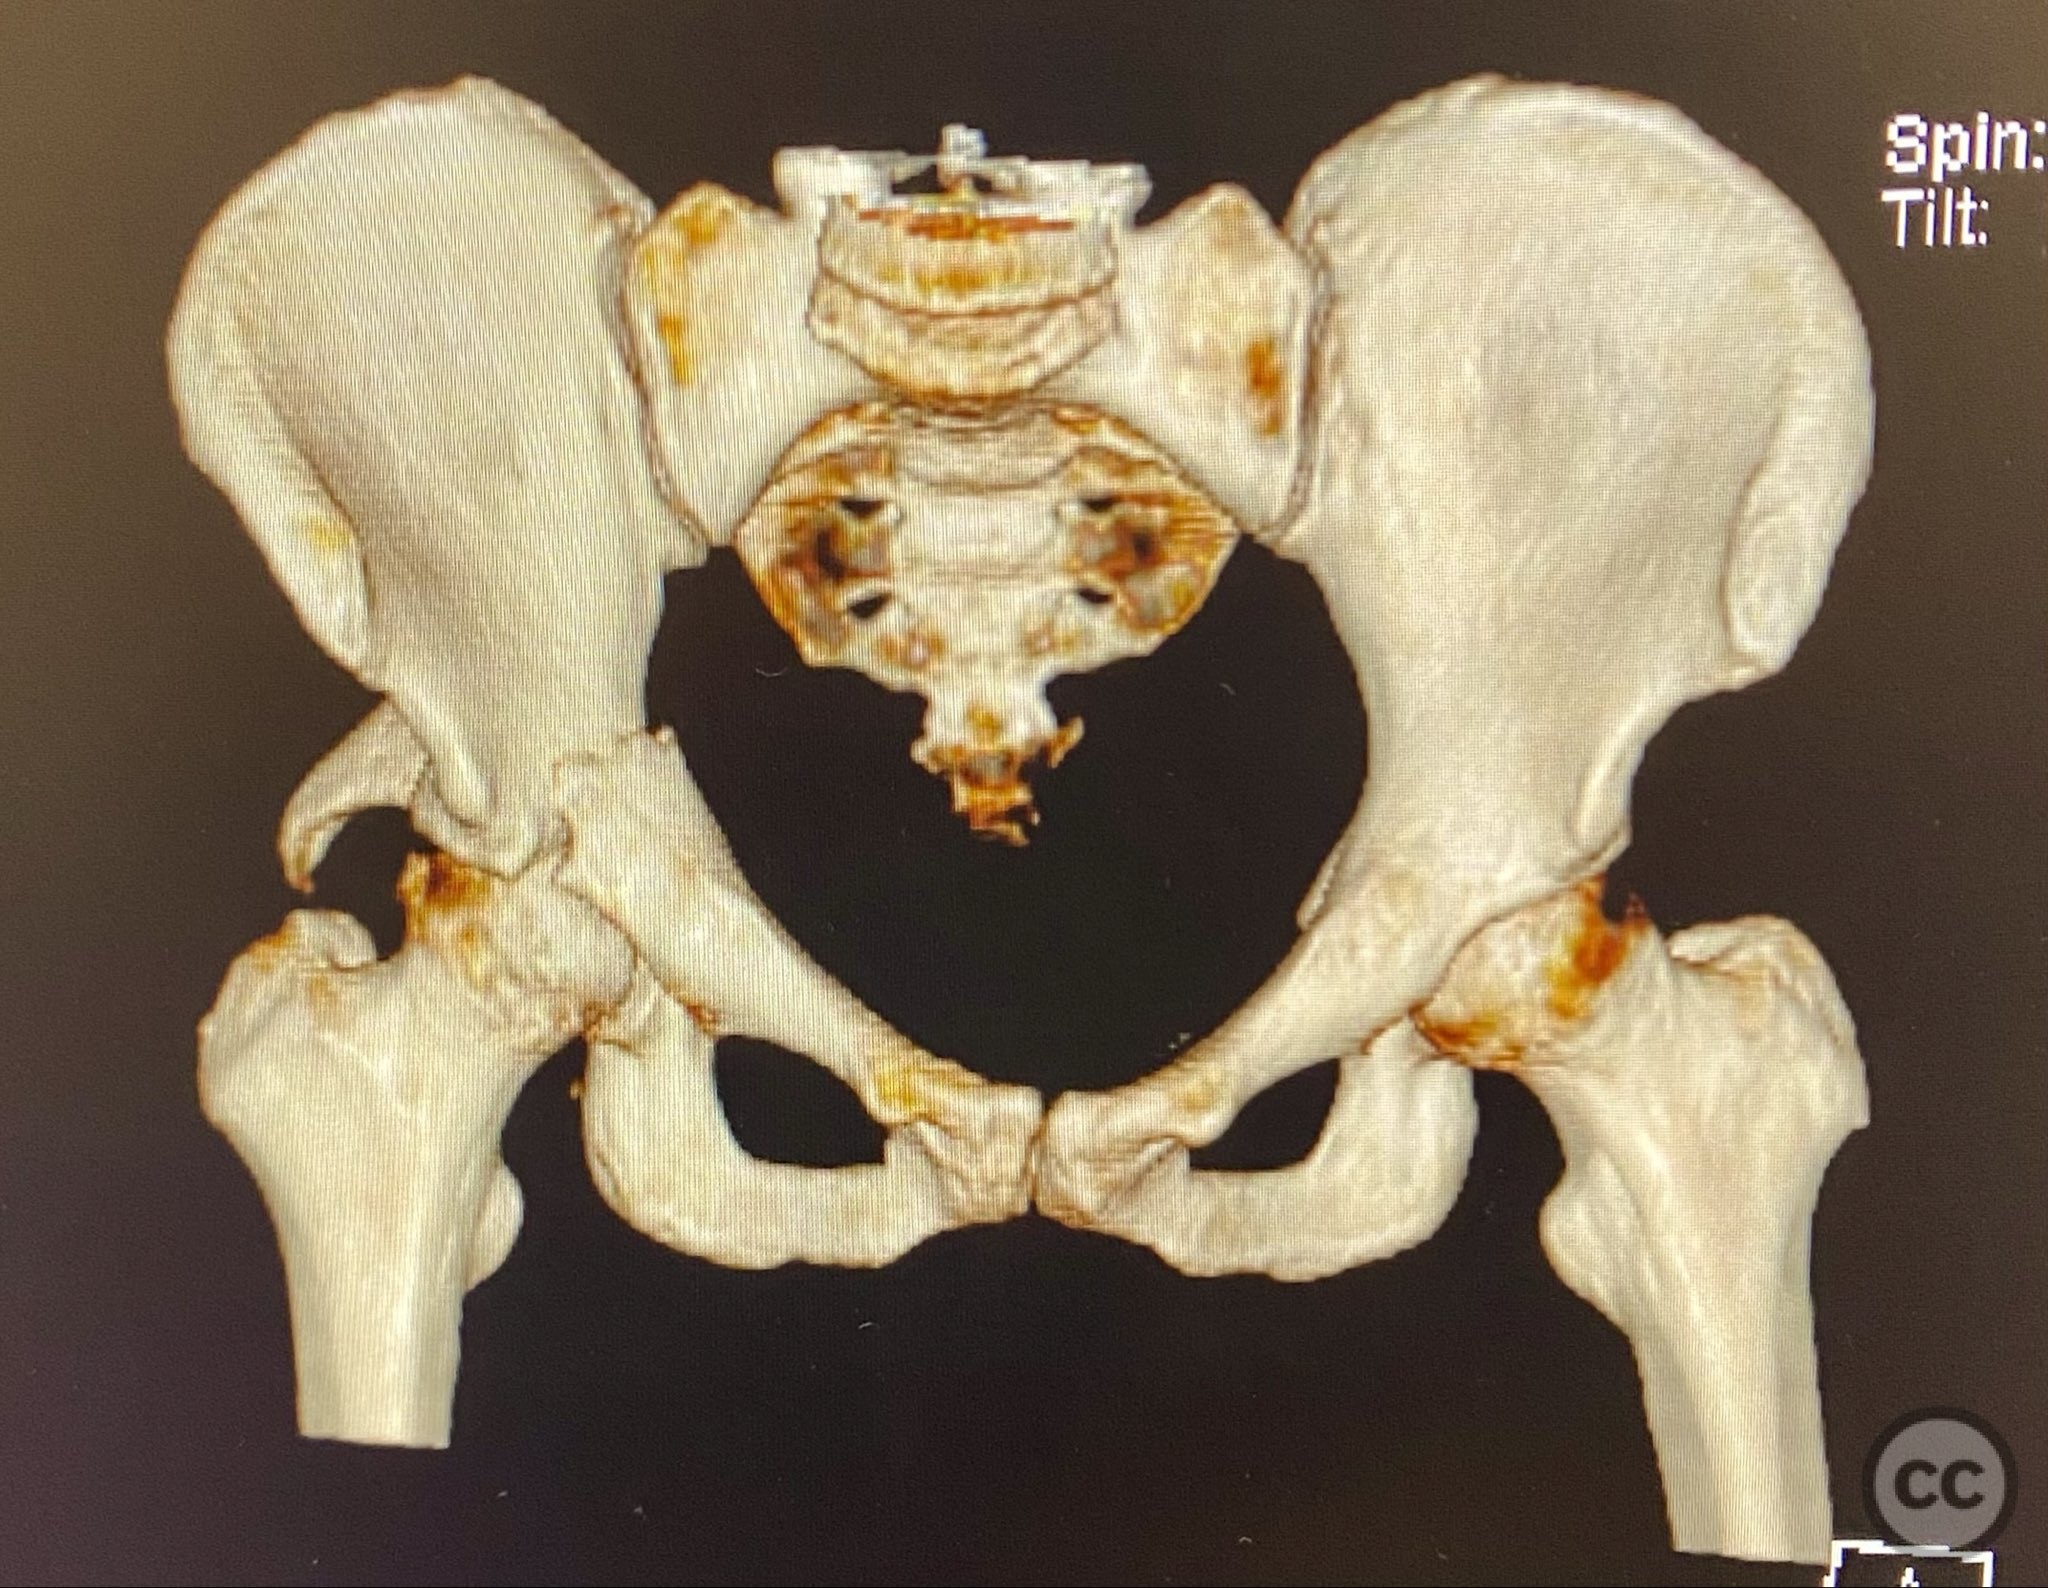

Clinical Details

Clinical and radiological findings:  A high-speed motor vehicle collision resulted in a closed transverse acetabular fracture with associated comminuted posterior wall (PW) fracture-dislocation. The femoral head exhibited impaction and comminution, with local cancellous bone crushed and the femoral head itself also sustaining compressive injury from the denser acetabular bone. Neurovascular examination was unremarkable. Initial CT imaging delineated the acetabular fracture planes, displacement, comminution of the posterior wall, femoral head impaction, and absence of soft tissue attachment to the caudal PW fragment.